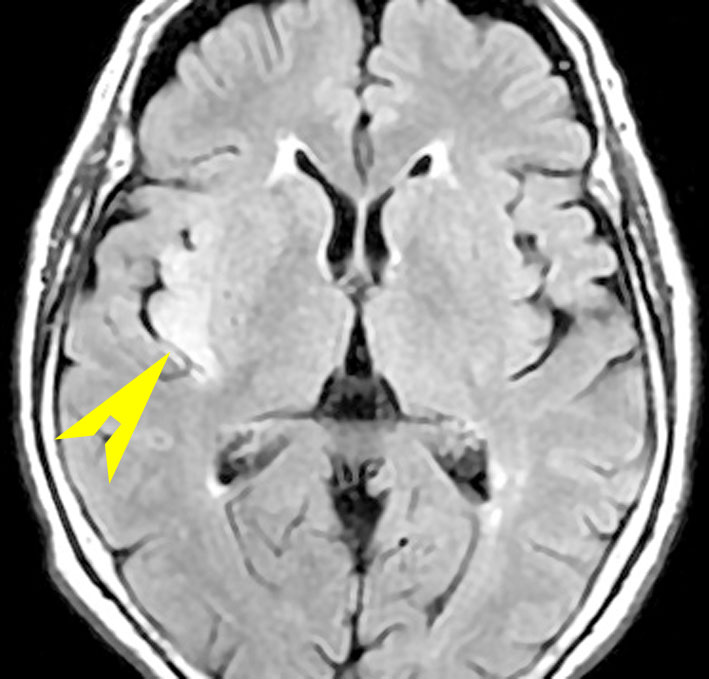

• MRI のT2・FLAIR(フレア)画像で淡く白く見える(高信号)のが特徴です

• 一般的には,びまん性で周囲がはっきりしない脳の中に「にじむような腫瘍」に見えます

• 初期には、一つの脳回に限局して境界が明瞭な小さな腫瘍として発見されることもあります (single gyrus glioma)

• ガドリニウム造影剤で増強されることはほとんどありません

フレア画像です。左上前頭回の星細胞腫ですが,境界がとてもはっきりしていて限局性 localized single gyrus glioma です。びまん性 diffuseには見えません。IDH1の変異があり,1p/19qの欠失はないので星細胞腫グレード2です。上の例とは全く違う臨床像を示しますが,分子病理でも区別はつきません。頑張って早めに全摘出して治してしまった方がいいタイプです。再発を避けるために,supratotal resectionと言って,周囲の正常脳組織も10mmくらい余分に摘出します。